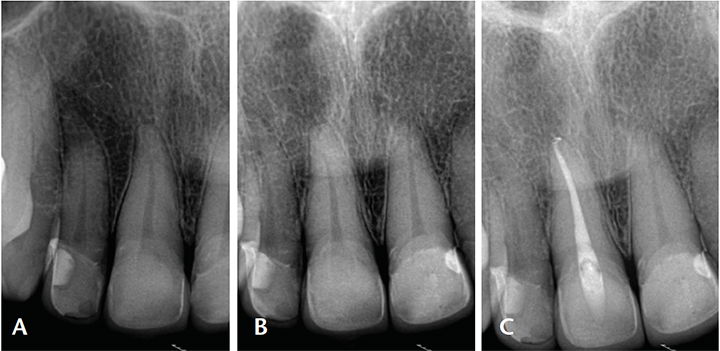

Root Canal Treatment

Root Canal Treatment is a procedure performed on the infected tooth to remove the decay affecting the pulp (underlying tissue containing blood vessels and nerve supply to a tooth). Simple filling procedure cannot restore a tooth’s dental health when the infection has encroached the pulp. Root canal therapy is the only alternative to save such tooth from being extracted. The main objective of root canal treatment is to preserve the infected existing natural tooth by disinfection. During a root canal therapy, access to the root canal present inside the root of a tooth is gained and the infected tissue is removed entirely. Hence Root Canal treatment bypasses extraction of the infected tooth and its replacement procedures thereby saving time and money.